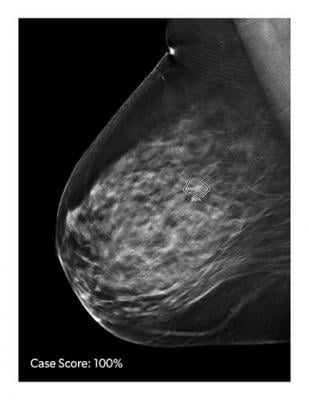

Computer-aided detection software helps doctors make more accurate diagnosis by assisting in the interpretation of medical images.